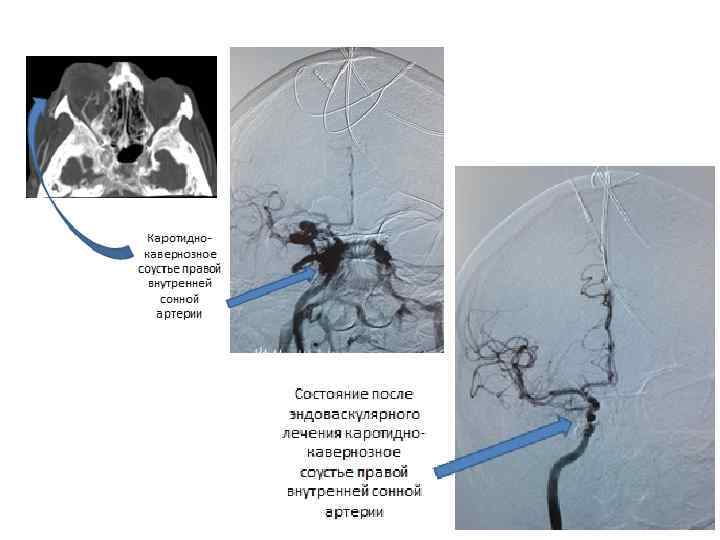

Лечение В типичных случаях осуществляют трансфеморальную (реже каротидную) катетеризацию пораженной ВСА катетером диаметром 8 -9 F (1 F = 0. 33 мм). Через него в сосудистое русло вводят баллон-катетер. Один (или несколько) баллонов последовательно вводятся в полость кавернозного синуса через разрыв в стенке артерии и после раздувания твердеющим силиконовым композитом сбрасываются в полость синуса, обтурируя соустье снаружи, сохраняя просвет ВСА. При невозможности реконструктивной операции выполняют баллон-окклюзию ВСА на уровне соустья.

До эмболизации После эмболизации